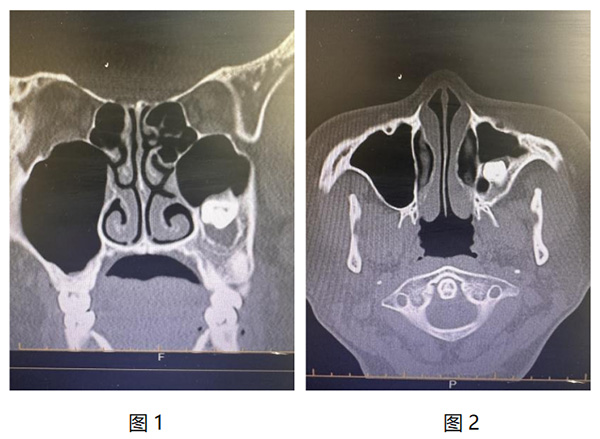

近日,我院耳鼻咽喉头颈外科成功为一名特殊病症患者实施了高难度手术。患者因“牙片检查时发现上颌窦阻生齿伴囊肿形成1月”入院,经鼻窦CT检查,可见其左侧上颌窦内存在高密度影,且周围有软组织包绕,诊断为上颌窦阻生齿伴囊肿形成。(图1、2)。